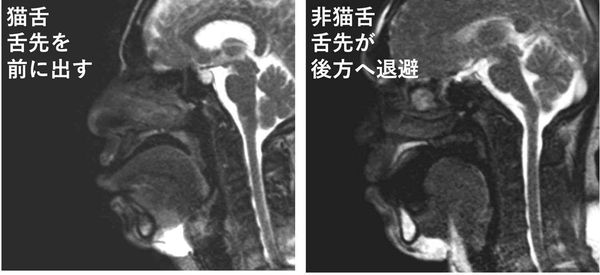

下の画像の左側が“猫舌群”、右が“非猫舌群”だ。 猫舌ではない人の場合、お茶が口に入ると舌が後方に移動して、下の歯と舌の間に“ポケット”を作り、そこにお茶を溜めている。そのあとで舌の周囲を伝ってのどへと流し込んでいくのだ。 一方の猫舌の人は、まず最初に舌先をお茶に接することからスタートする。非猫舌群の人が終始舌先をお茶に接しないようにしているのとは正反対の動きだ。 熱いものを食べる時には意識的に舌は奥へと引っ込め、舌の下のポケットに一旦収めるようにトレーニングすればいいのだ。